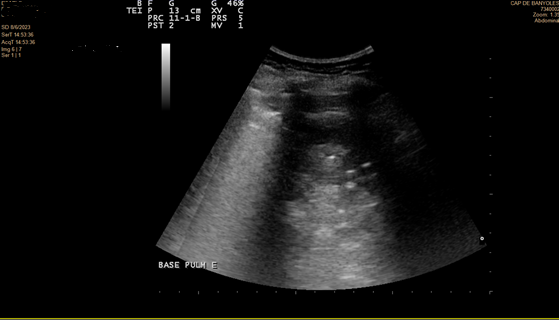

Se realiza ecografía pulmonar a pie de cama.

En la ecografía se objetiva irregularidad en la línea pleural, líneas B coalescentes (light beam) y un patrón de consolidación pulmonar en ambas bases pulmonares (I > D).